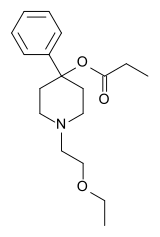

4-Phenylpiperidines

Pethidines (meperidines)

Structures